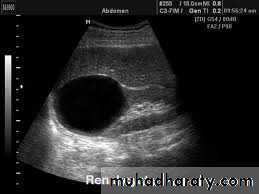

US :-

shows echo-free cystic lesion with posterior enhancement.